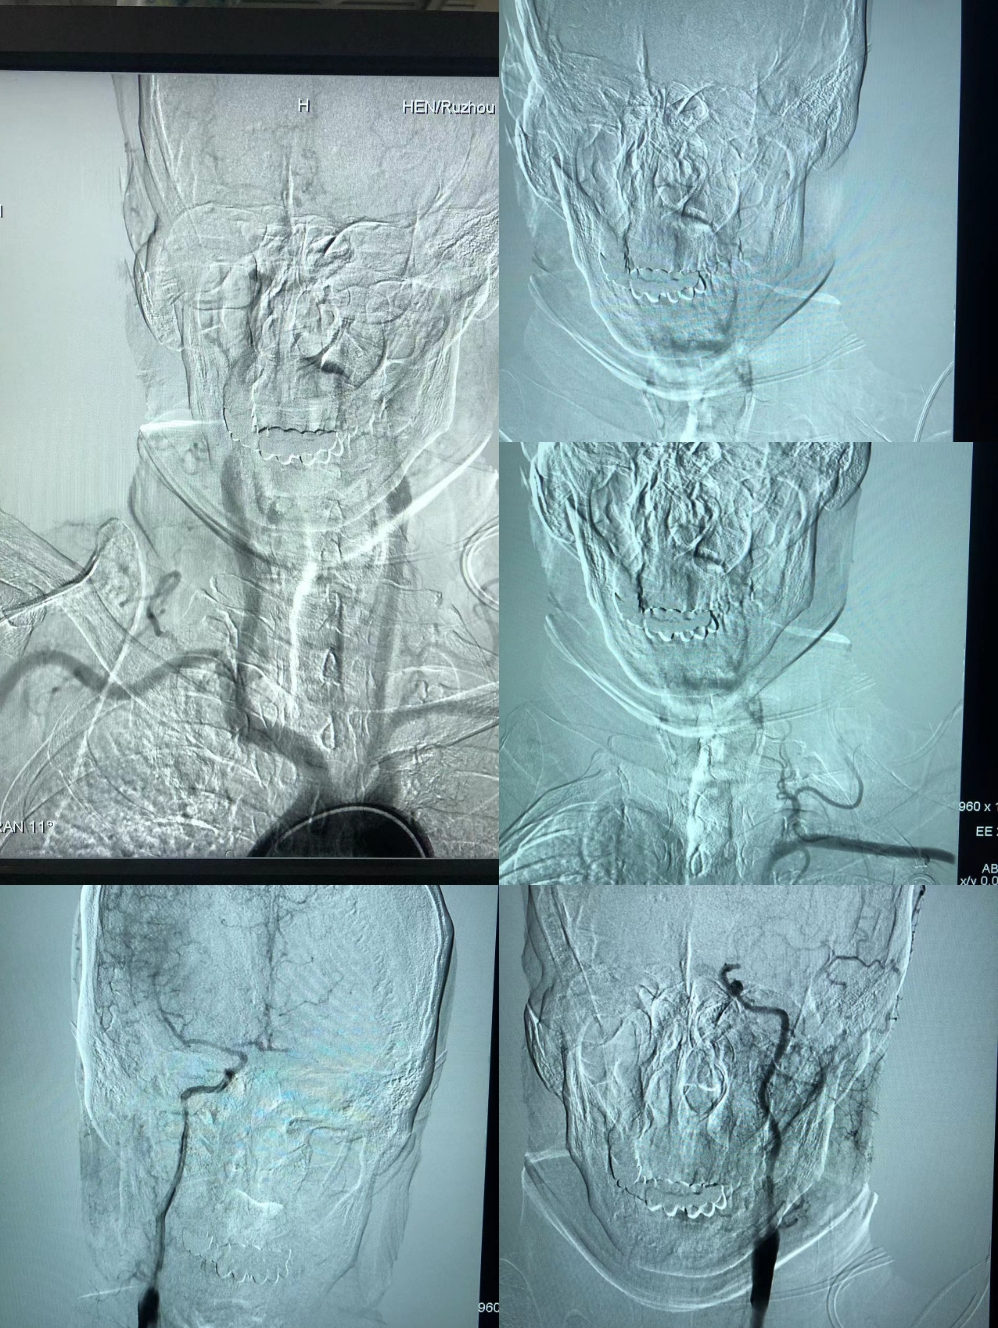

造影:左侧大脑中动脉闭塞,左侧椎动脉闭塞。

8FGuilding+6F115Navien建立通路。

Synchro200mm微导丝配合Rebar18微导管穿越闭塞段,经Navien及微导管造影提示闭塞段位于左侧大脑中动脉中段,闭塞段很短,推测血栓负荷量极少。

送入300mmSynchro微导丝,Gateway2.5*9mm球囊扩张后,观察血流,出现弹性回缩。再次扩张后,撤出球囊,交换PLUS导管,送入Enterprise4.0*23mm支架,顺利释放,血流维持可,轻度残余狭窄。